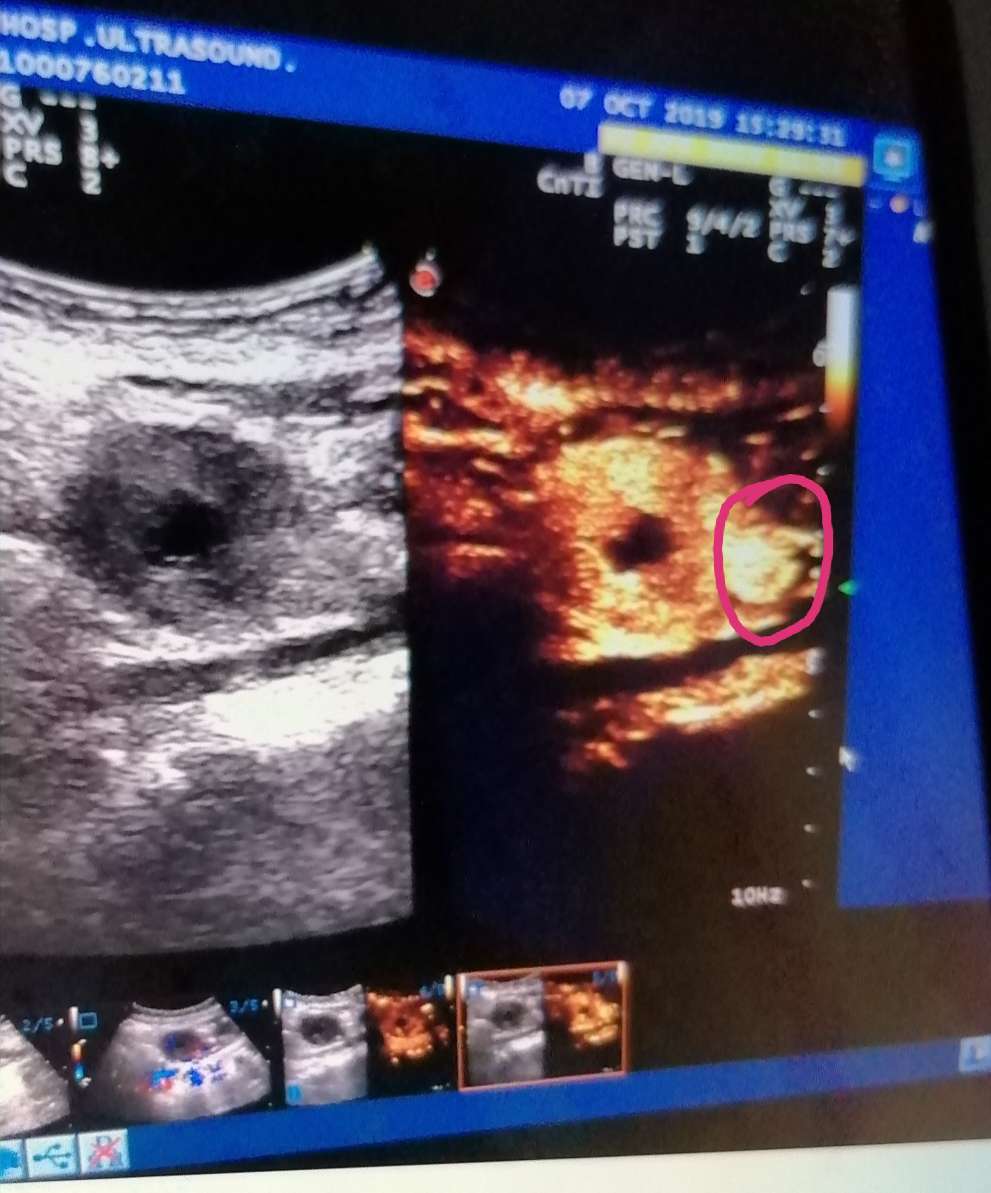

第五十个疗程开始了,今天又投入新的一轮疗程治疗,上几个疗程有很大的收获,图一的白点基本钙化打死,这次复查超声造影基本看不见了(图2),这也是我五年来又一个收获,愿后续治疗把我原病灶早日消灭,身体越来越好!让我能平平安安健健康康度过我的一生!